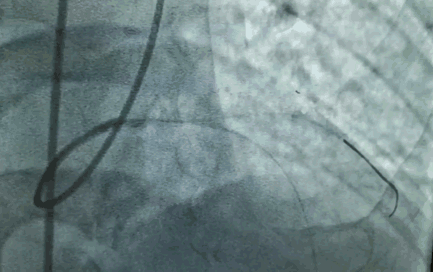

术前就和周玉杰教授团队做了周密研讨和细致评估,包括体外模拟植入瓣膜后的冠脉情况。术中,也做了多种应急预案,一方面备了体外循环机器,万一不行,就转机上体外循环支持;另一方面,在左冠主干的位置放了导丝,如果造成左冠动脉缺血,会立即行冠状动脉球囊扩张➕支架植入治疗。

在瓣膜的选择上,也充分考虑到冠脉开口位置低、主动瓣左冠的窦部比较小的问题,最终采用16mm球囊预扩,20mm瓣膜释放,一个半小时左右的手术过程顺利,冠状动脉开口没有受到影响,冠脉的供血也比较好。